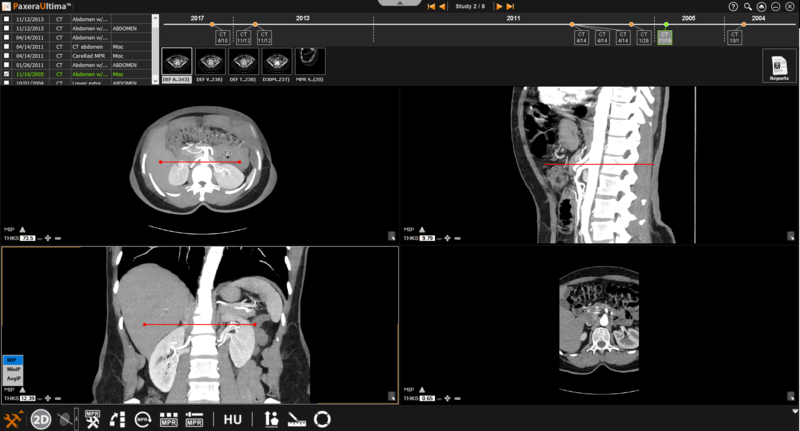

» Adjust line position - The positions of the lines can be adjusted by clicking on the line of interest and dragging it in the direction of interest.

» Adjust line angle - The angle of the lines can be adjusted by clicking on the circle at the end of the line and dragging it in the direction of interest.